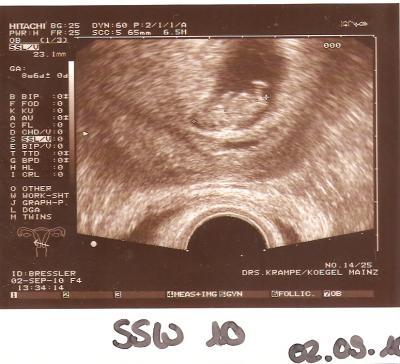

Hallöle, wie angekündigt hab ich nun auch das Ultraschallbild von der gestrigen Vorsorge :-).

Bild zu Ultraschallbild von VS gestern - Forum für März - Mamis

Süß, ganz eingekuschelt mit den Füsschen nach oben, wenn ich das richtig sehe lg